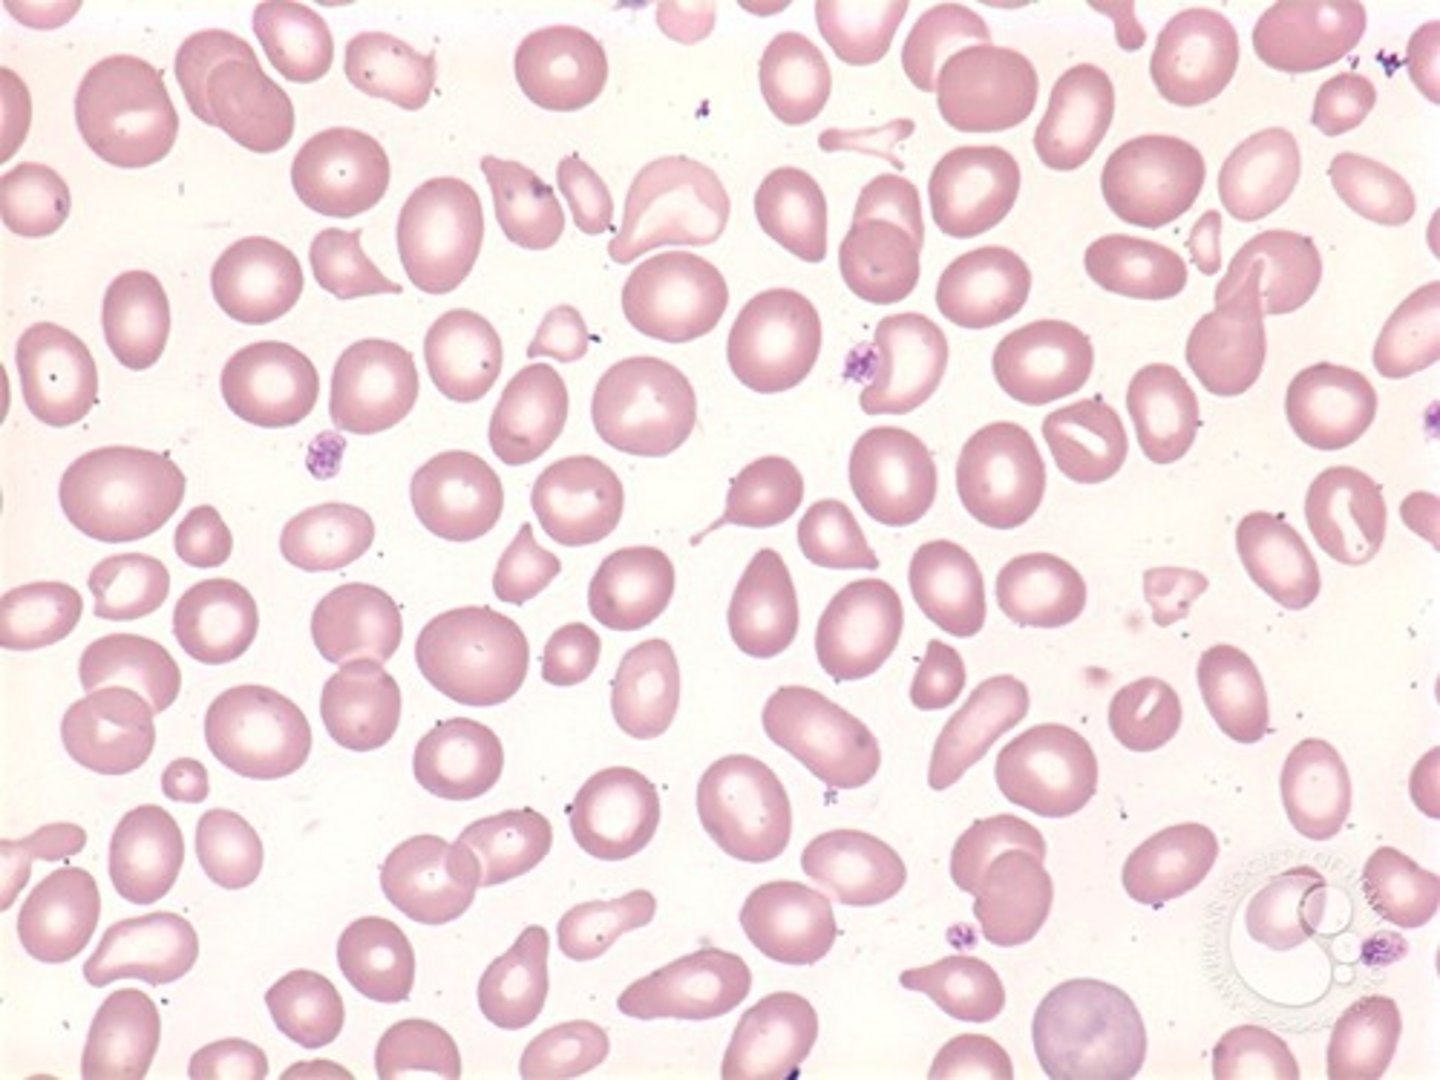

dacrocyte

tear drop shaped RBC's

-distinctive "point" at one end

poikilocytosis

variation in the shape of RBC's